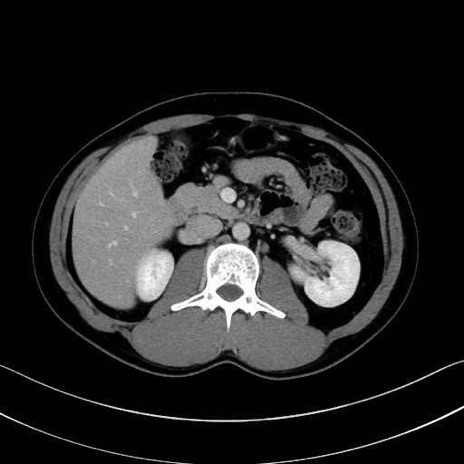

【症例】20歳代 男性 スクリーニング

■起始:典型的には腹腔動脈幹(celiac trunk)から左胃動脈・総肝動脈とともに三分岐し、脾動脈は左後上方へ向かう。

■走行:膵上縁または膵実質背側を蛇行しながら左方へ進み、膵尾部近傍で脾門へ至る。蛇行の程度は個体差が大きい。

■終枝:脾門部で複数の終末枝に分かれ、上極・下極枝や脾門枝群を形成する。胃短動脈群や左胃大網動脈はしばしば脾動脈から分岐する。